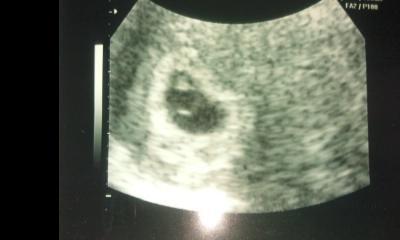

poszi, nagyon dögös ez a lurkó!